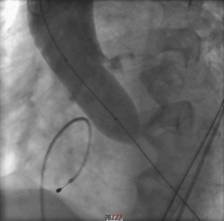

经过周密的筹备,3月5日上午,何贵新主任团队在广东省心血管病研究所罗建方教授团队的指导下,“临时起搏器植入、鞘管植入、跨瓣、球囊扩张、精准定位、瓣膜释放.......”,历经1小时余,顺利为韦奶奶行经导管主动脉瓣置换术(TAVR),置入新的主动脉瓣,打开心脏血液流出的第一道门,手术创口仅针眼大小。术后,复查超声心动图提示人工主动脉瓣膜工作良好,心脏血液泵出顺畅,术前跨瓣压差62 mmHg术后降至差2mmHg,手术非常成功,术后第2天即可下床活动。

另外一例患者谢爷爷面对一场惊心动魄的“生死战”。首先,在球囊抵达主动脉瓣口,刚准备扩开为瓣膜植入创造条件时,瞬间出现室颤,心跳骤停。“快,除颤、心肺复苏!”团队医护人员迅速抢救,同时另一组人将瓣膜送入心脏,跨瓣压差由术前127mmHg降至术后3mmHg。术后送入ICU治疗,第3天,谢爷爷病情稳定,即可下床活动。